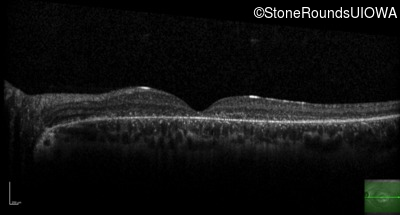

AR Stargardt Disease (IIA)

AR Stargardt Disease (IIA)

| Age at visit: 12 years |

| Age at visit: 13 years |

| Age at visit: 15 years |